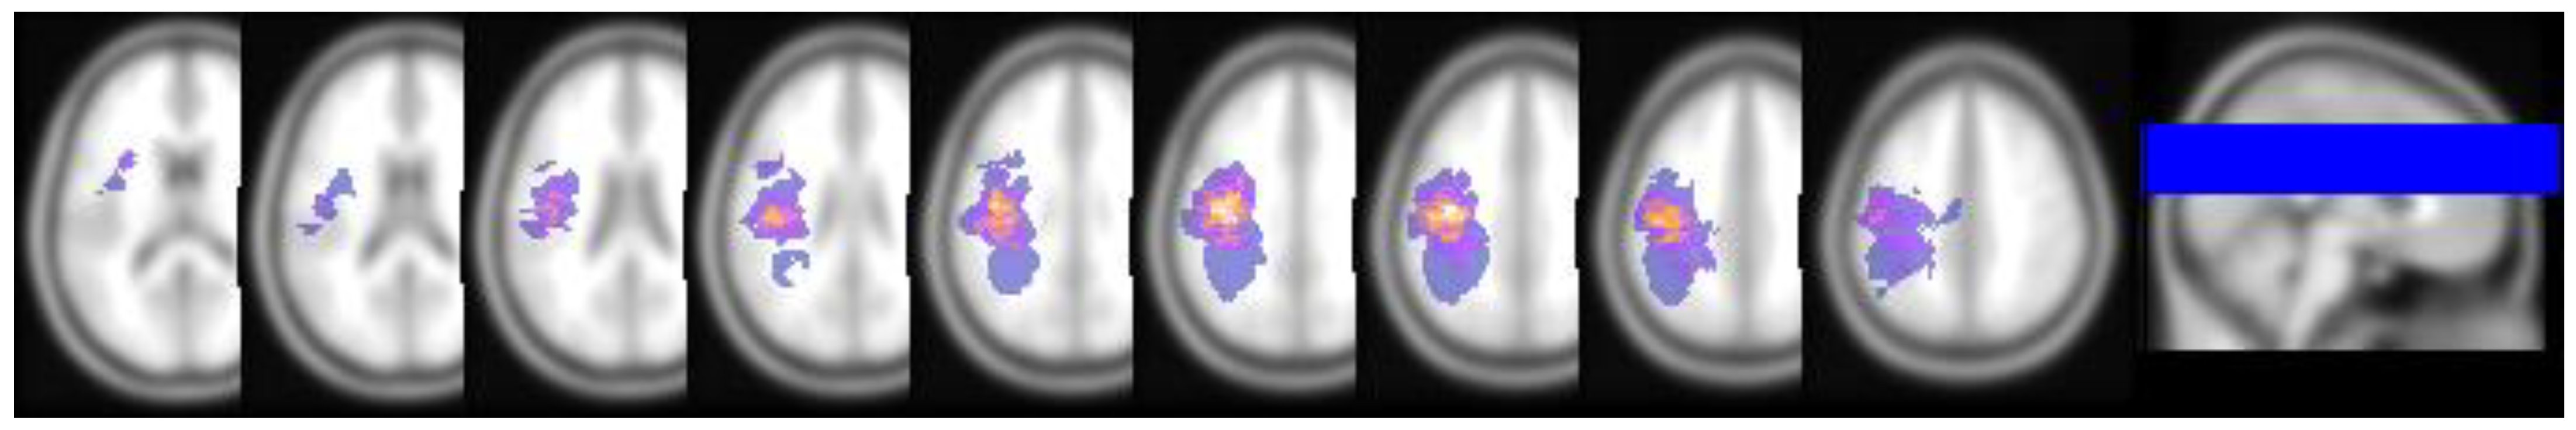

2. Materials and Methods

2.5. Tumor Region of Interest Extraction